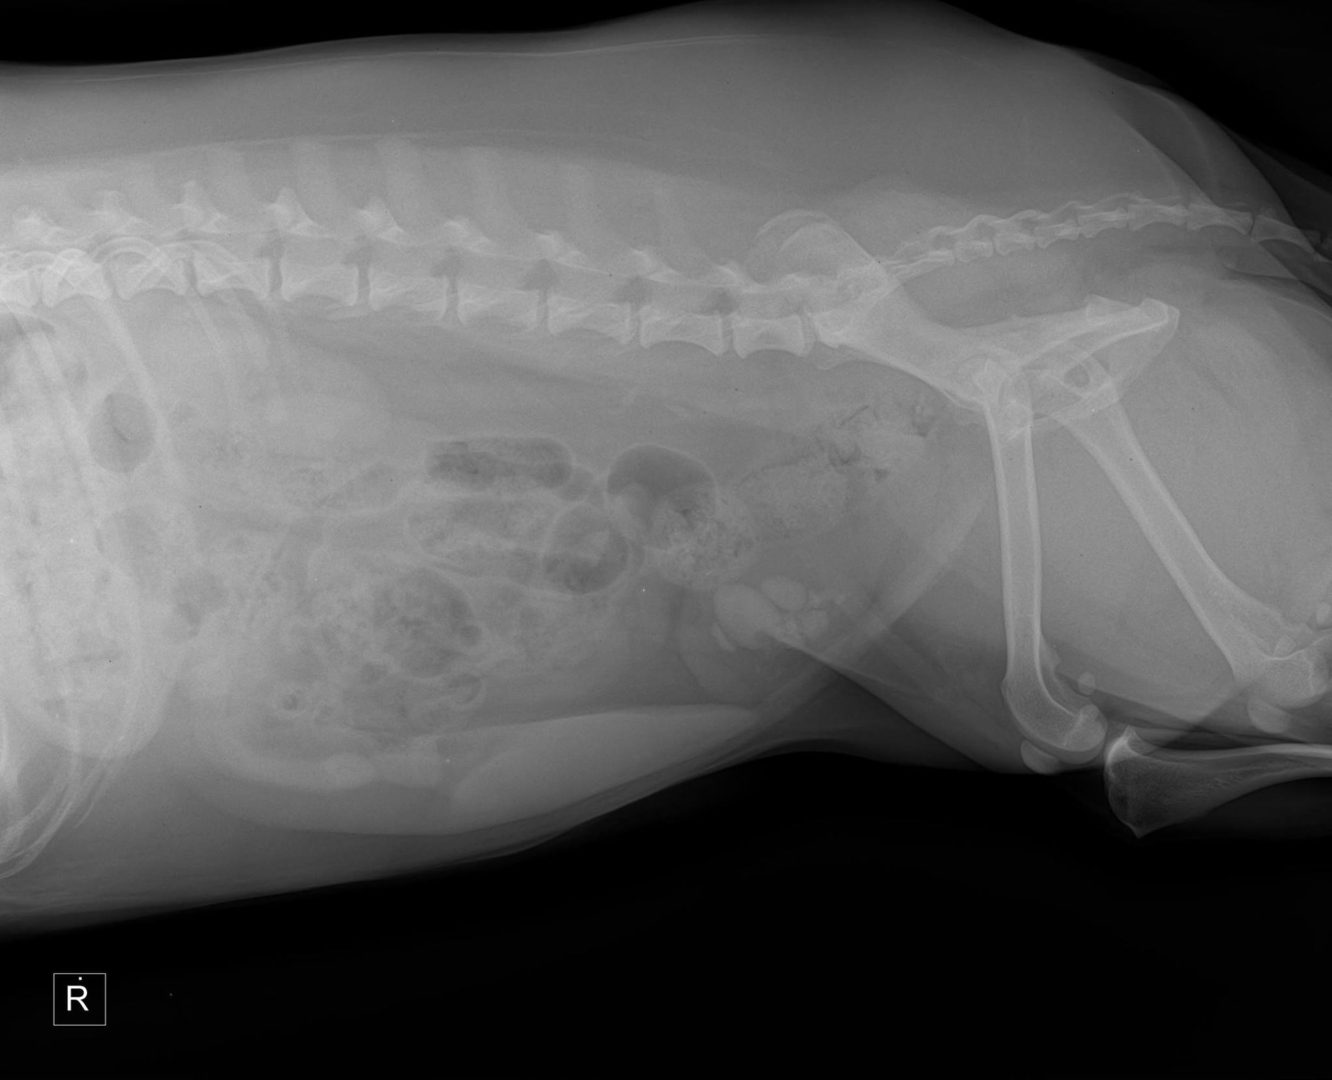

This is a case of a 10-year-old female spayed Boxer who has been anorexic intermittently for several weeks. Over the last week, the owner has had to syringe feed. Prior to onset, P was treated for cystitis, which resolved. Treatment for gastritis, including sucralfate, famotidine, and triamcinolone was only effective for a few days at a time. Chemistries on April 25 showed a slight elevation of lipase. CBC had very mild lymphopenia. Previous surveys' results were unremarkable for GI. Only 2 instances of vomiting have occurred during this time.

On the survey study you can see a soft tissue opacity in the stomach. However, be careful not to overinterpret this on a non-contrast image. Fluid in the stomach can often have this appearance and you can get a false impression of gastric wall thickening due to the air/fluid interface. However post adminstration of barium, we can now see a gastric mass causing a filling defect in the gastric wall on numerous images, and this confirms that what we saw on the survey images was a real finding. The contrast will surround the mass causing it to appear radiolucent and allowing us to define the margins. Primary differentials, particularly in this age and breed, would be neoplasia (lymphoma, adenocarcinomva).

Would you see this on ultrasound? Potentially, but it depends on your skill level in sonography, how much air is in the stomach, where in the stomach it is located, etc. So if you do not have access to ultrasound (or even if you do) or if you were unable to get a good view of the gastric wall this is a great study to do! Thank you to Dr. Greg Emmert (one of my vet school classmates!) and McGee Street Animal Hospital for this fascinating case!